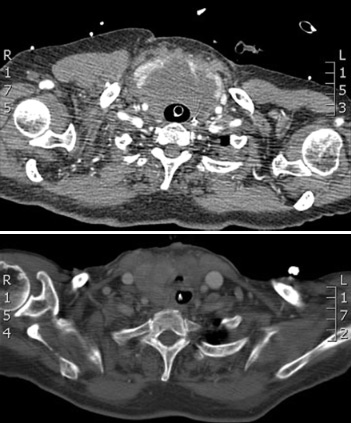

El tratamiento es quirúrgico, si es posible.[Figure caption and citation for the preceding image starts]: TC de cuello pre y posoperatorio: compresión traqueal por un linfoma de tiroidesVan la Parra RFD, Kroeze J, van Die J, et al. Progressive respiratory distress due to neck mass. BMJ Case Reports. 2009; doi:10.1136/bcr.11.2008.1193 [Citation ends].